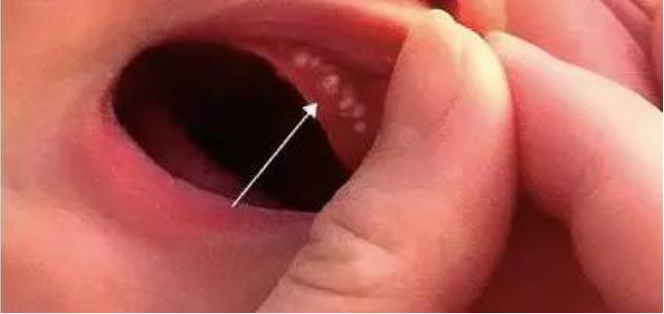

十二、口腔:

新生儿牙龈上出现的黄白色小颗粒,称为马牙,硬腭中线上大小不等的黄色小结节,称为彭氏珠,都是由于上皮细胞堆积形成,可自行消退,切勿挑破,以防感染。两侧颊部各有一个隆起的脂肪垫,称为“螳螂嘴”,有利于吸吮乳汁,不可挑破。